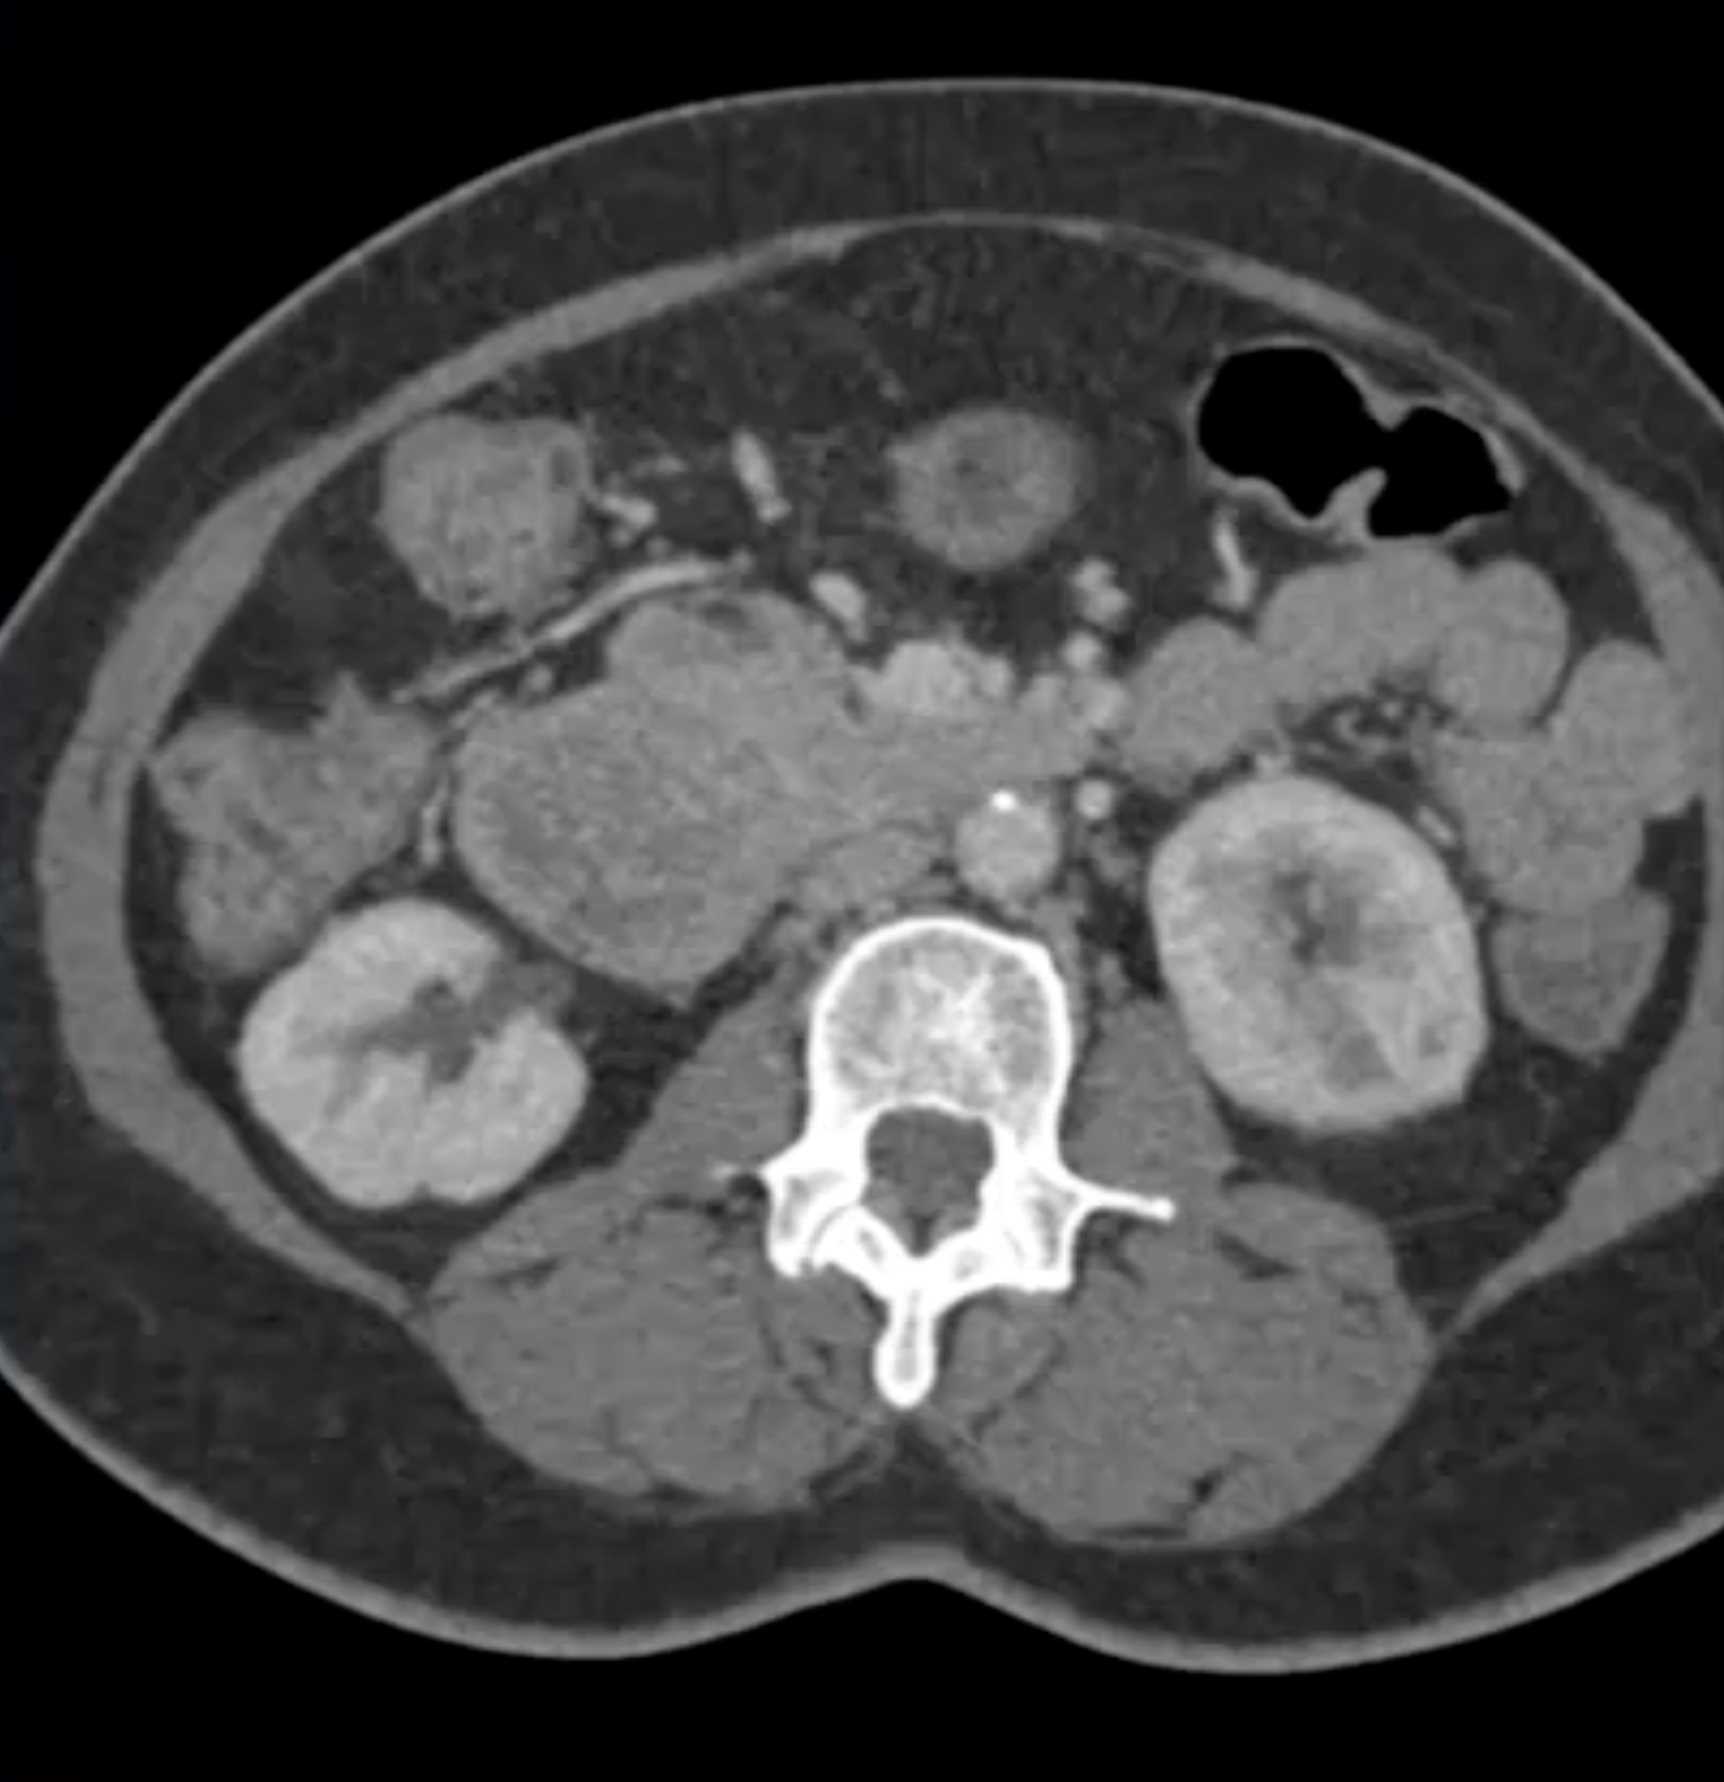

Lagre Gastric GIST Tumor